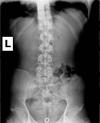

LAT Lumbar

Hey! My name is Kiko and I am an x-ray tech at a chiropractic practice. I have a fusion of my transverse processes of my L5 to S1, and I was looking for another set of eyes on it. I practice yoga and I notice that any forward folds and back-bends cause a lot of pain. I also have extremely tight hamstrings, which I'm sure contribute to the pain. I was just wondering if you guys could look over these and give me some detailed analysis.

Certainly you have a transitional segment at the the lumbosacral junction. S1 has a large spatulated transverse process on the left which appears to articulate with the sacrum - you can see the sclerosis. I don't see any fusion to the SI. The facets are difficult to visualise. Rudimentary ribs at L1 as is common with a lumbarisation of S1.

Also a very small pincer deformity in the left hip; any groin pain or stiffness?

I'd also be looking for abnormal motion palpation findings at L2 and L3.